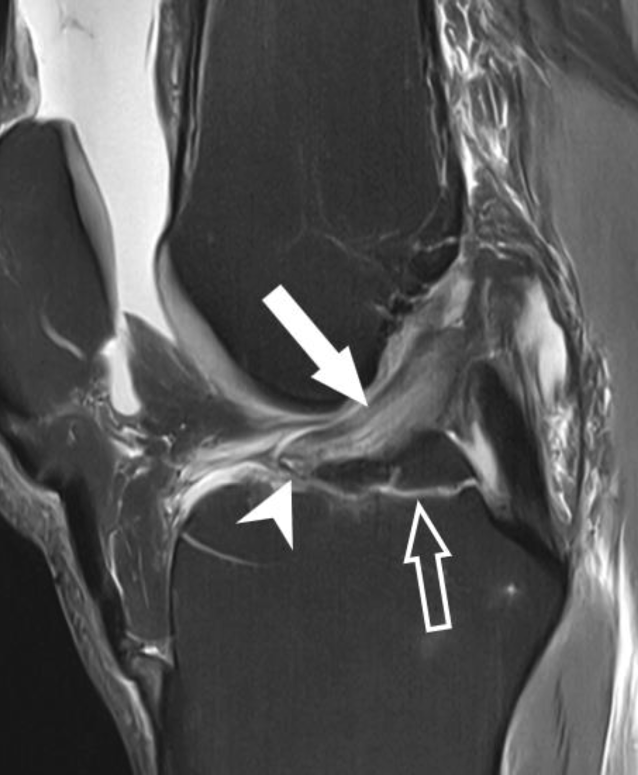

Abb. 4

MRT des Kniegelenks mit einer axialen protonendichtegewichteten (PD) Sequenz mit Fettsuppression. Die Schichtführung auf Höhe der Femurkondylen zeigt eine vollständige Avulsion des vorderen Kreuzbands (VKB) vom femoralen Ursprung (Pfeil). Diese Rupturen sind in manchen Institutionen von besonderem Interesse, da sie sich für primäre VKB-Reparatur mit Erhalt des nativen Ligaments eignen. Gelegentlich finden sich schwache subkortikale Knochenmarködeme (hohler Pfeil) am femoralen Ursprung des VKB, welche möglicherweise im Rahmen eines assoziierten Zugs am Periost erklärt werden können